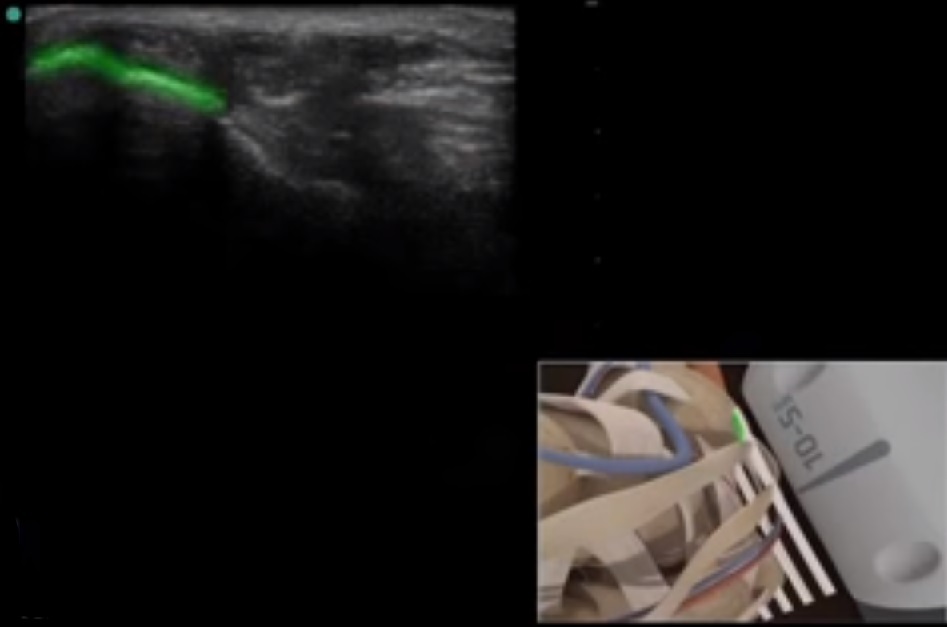

Bild: Fuß und Sprunggelenk, medialer Malleolus

Markierter Bereich: medialer Malleolus